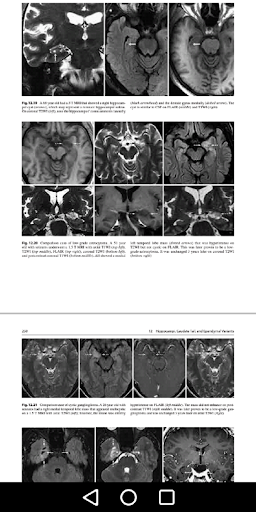

Aplikasi ini membentangkan variasi pengimejan biasa dari otak, tengkorak, dan vasculature craniocervical. Pengimejan Magnetic Resonance (MR) dan tomografi yang dikira (CT) telah mendirikan secara dramatik dalam tempoh 10 tahun yang lalu, terutamanya dalam hal teknik baru dan pencitraan 3D. Salah satu masalah utama yang dialami oleh ahli radiologi dan ahli klinik adalah tafsiran varian normal berbanding dengan keabnormalan yang varian mimik. Melalui koleksi imej yang luas, aplikasi ini menawarkan spektrum penampilan untuk setiap varian dengan pengimejan 3D yang disertakan untuk pengesahan; meneroka artifak biasa pada MR dan CT yang mensimulasikan penyakit; membincangkan setiap varian dari segi anatomi yang berkaitan; dan membentangkan kes perbandingan untuk tujuan membezakan penemuan biasa dari keabnormalan. Ia termasuk kedua-dua varian biasa serta varian yang baru dikenal pasti yang divisualisasikan oleh teknik-teknik yang baru dibangunkan seperti pengimejan berwajaran dan multidetector / multislice ct. Aplikasi ini juga menyoroti varian pengimejan biasa dalam kes-kes pediatrik.

Atlas variasi pengimejan biasa dari otak, tengkorak, dan craniocervical